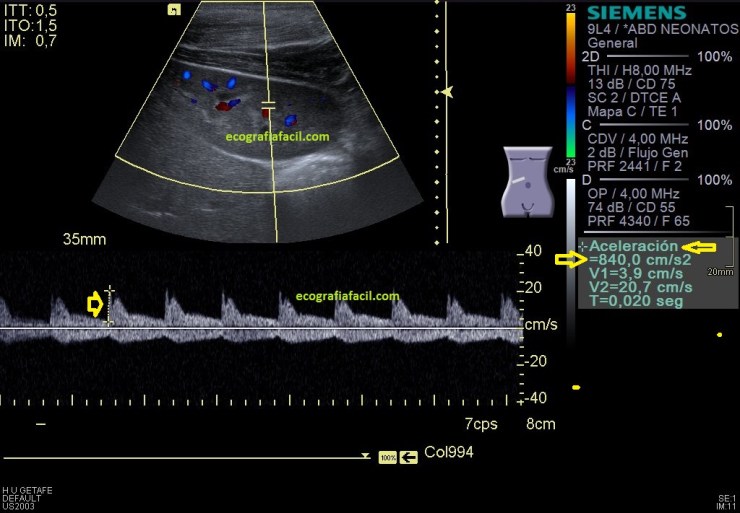

En la imagen 11 vemos una valoración cuantitativa en doppler espectral con valores señalados de 840 cm/sg de aceleración, que es muy importante que esté en valores superiores a 300 cm/sg para ser normal y se mide en la fase de sístole, al comienzo, en la primera pendiente, que corresponde con la R del trazado electrocardiográfico, hasta que esta pendiente llega a lo más alto o hace una ligera bajada. Observa en la imagen 11 donde se hace la medida y compara con la imagen 14, cómo el espectro es diferente, es normal.